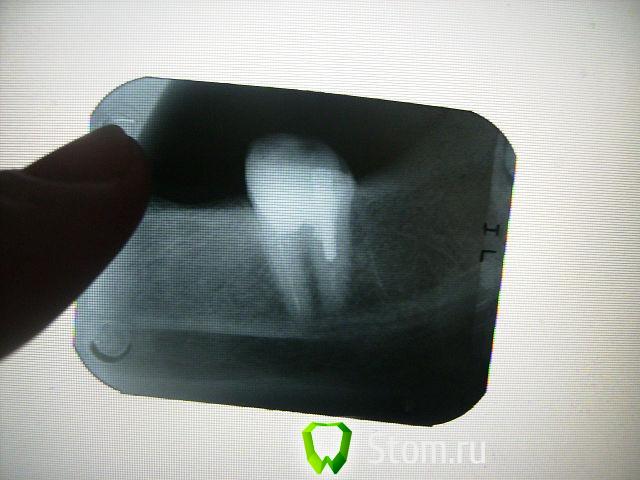

болящая Опубликовано 3 января, 2012 Поделиться Опубликовано 3 января, 2012 Уважаемые доктора! Перелечивала леченый 10 лет назад резорцин-формалиновый зуб (37).После перелечивания все дни боль при накусывании и ноющая самопроизвольная (10 дней) .Через 10 дней от перелечивания-свищ со щечной стороны с гнойным отделяемым ,боль ушла.Все дни обращалась к лечащему врачу. Ответ - все хорошо, на снимке каналы запломбированы отлично,а свищ-это реакция на перелечивание.То же сказал ортопед и закрепил мост на временный цемент (мост МК).Так ли хорошо на снимке с каналами,через неделю ставить мост на постоянный цемент, МК вещь не дешевая, что бы ее потом ломать. В настоящее время свищ закрылся, зуб не болит. Заранее спасибо за ответы. Ссылка на комментарий

DokDent Опубликовано 3 января, 2012 Поделиться Опубликовано 3 января, 2012 Уважаемые доктора! Перелечивала леченый 10 лет назад резорцин-формалиновый зуб (37).После перелечивания все дни боль при накусывании и ноющая самопроизвольная (10 дней) .Через 10 дней от перелечивания-свищ со щечной стороны с гнойным отделяемым ,боль ушла.Все дни обращалась к лечащему врачу. Ответ - все хорошо, на снимке каналы запломбированы отлично,а свищ-это реакция на перелечивание.То же сказал ортопед и закрепил мост на временный цемент (мост МК).Так ли хорошо на снимке с каналами,через неделю ставить мост на постоянный цемент, МК вещь не дешевая, что бы ее потом ломать. В настоящее время свищ закрылся, зуб не болит. Заранее спасибо за ответы. Я ничего хорошего не вижу.Свищ может открыться снова при обострении процесса. Ссылка на комментарий

DokDent Опубликовано 3 января, 2012 Поделиться Опубликовано 3 января, 2012 Спасибо за быстрый ответ! А можно поконкретней-что не так? Предположения любознательного рентгенолога,что есть еще один канал,который не пройден ни10 лет назад,ни сейчас.Неоднократные ответы доктора-все отлично,ничего болеть не может.Больше всего вводит в сомнение фраза-формирование свища при перелечивании каналов- благоприятный исход,свищ закроется и все будет хорошо! Каналы должны быть хорошо расширены,промыты и запломбированы на всём протяжении.На Ваших снимках этого нет.Если они плохо расширены,следовательно недомыты и незапломбированы как надо.Обострение периодонтита при перелечивании возможно,но если лечение проведено правильно-всё проходит,а если нет-может периодически повторяться. Ссылка на комментарий

болящая Опубликовано 4 января, 2012 Автор Поделиться Опубликовано 4 января, 2012 Зуб после первого посещения выглядел так(убрали старую пломбу,прошликанал 1-й и частично 2-й),временная пломба.Качество снимка отвратное.но другого нет. Ссылка на комментарий